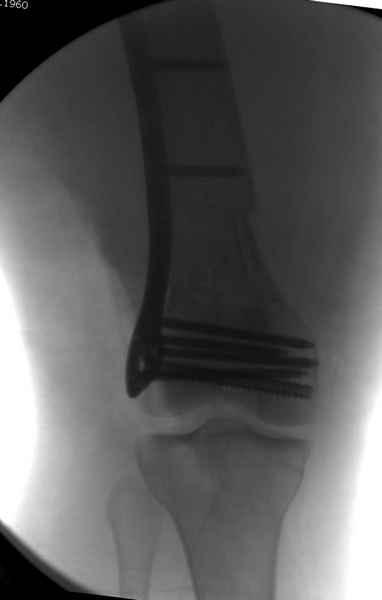

Уважаемые коллеги! От имени Алексея Смирнова всем спасибо за обсуждение. Больной прооперирован. Снимки в приложении.